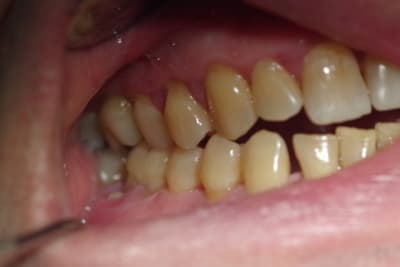

Le patient de 65 ans n'a plus d'occlusion sur le secteur ant et sur le secteur postérieur gauche.

L'occlusion ne se fait que sur les 5, 6 et 7 côté droit.

De ce fait la surcharge occlusale sur la 46 a entraîné une lyse osseuse importante qui contre indique la conservation de cette dent.

J'ai d'abord pensé adresser le patient pour une rééducation linguale ( kiné ou orthophoniste) car le patient a une langue très puissante qui a entraîné l'inocclusion totale des secteurs antérieurs et latéraux ( côté gauche).

A priori le patient m'a juste rapporté un épisode de blocage il y a 2-3 mois mais cela n'a duré que qq secondes. A la palpation je ne sens pas de vacuité au niveau de la cavité glénoîde. L'ouverture me semble légèrement asymétrique mais il n'y a aucun craquement ni douleur à ce moment là.

Je pencherai plutôt vers une déformation de son maxillaire due à une pulsion linguale importante.